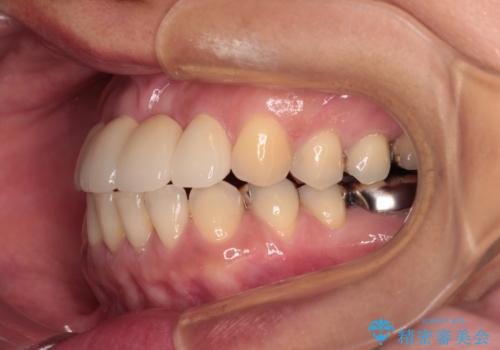

中途半端な矯正治療と前歯の欠損 再矯正とオールセラミッククラウンによる補綴治療

- 矯正治療を行ったものの、隙間やデコボコが多く、欠損している前歯も気になるとのことで来院された患者様です。

当初はセラミック治療だけを希望されていましたが、上下前歯のデコボコが顕著であったため、セラミッククラウンにて治療する前に再度矯正治療を行った方が仕上がりがきれいになると説明し、再矯正を行うこととしました。

矯正治療により前歯横幅のバランスを整えた後に、上顎前歯をオールセラミックブリッジにて補綴治療を行うこととしました。